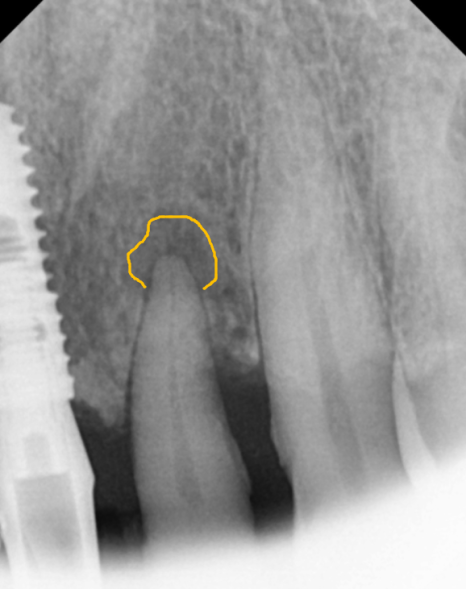

방사선 사진상,

치아 뿌리끝 염증도 진행되었고

뼈가 녹아 흔들림도 있던 상태라

231107 뿌리 끝 염증으로 뼈가 녹은 모습

방사선 사진상, 뿌리끝 염증으로

뼈가 녹은 부위가 있었고,

뼈 폭도 얇아 임플란트만 식립하기엔

무리가 있어 보였습니다.

231107